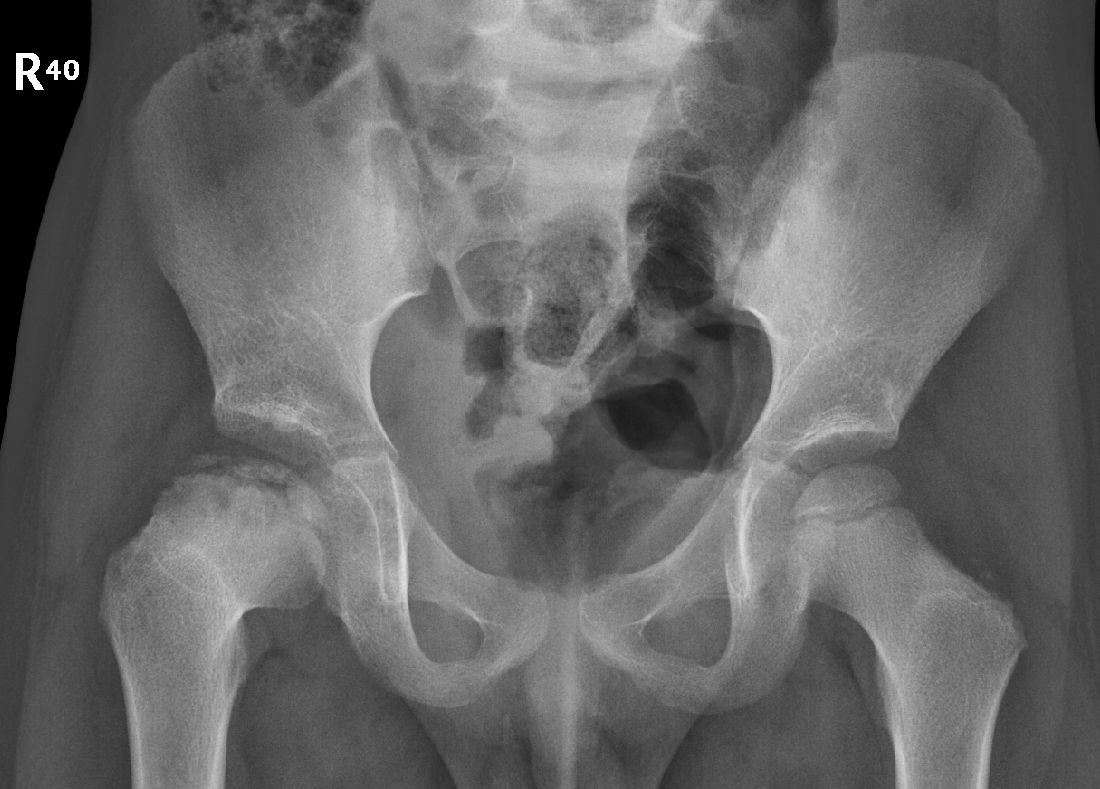

4 years old child with painful walking on the right thigh.

No history of trauma.

Diagnosis ?

Legg-Calve-Perthes.